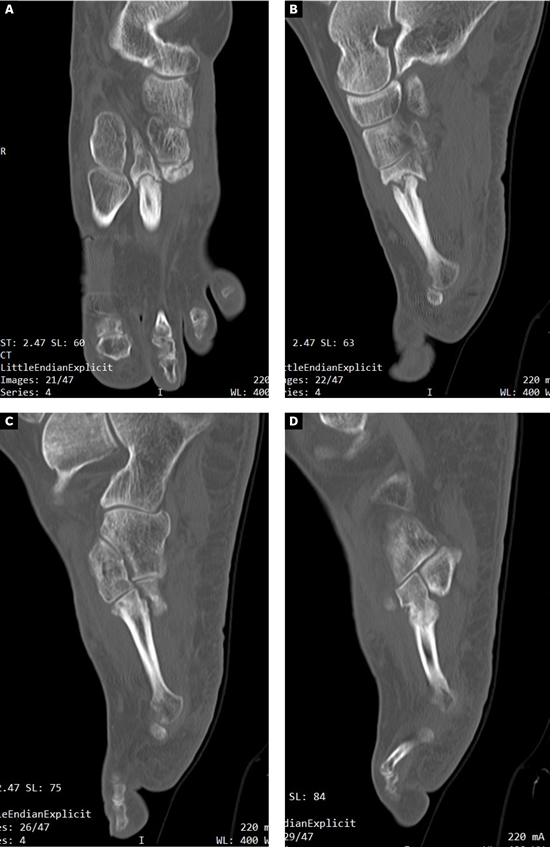

Se realizó radiografía dorso-plantar en carga del pie derecho (Figura 1) que mostraba una imagen radiológica compatible con ausencia de consolidación de las osteotomías en las bases de 2.º, 3.º y 4.º metatarsianos, además de la presencia de hallux abductus valgus. Se solicitó una tomografía axial computarizada (TAC) para estudiar más detenidamente el estado actual del proceso de consolidación ósea. La paciente acudió con resultado de TAC el 5 de mayo de 2015, donde se evidenció la ausencia completa de consolidación ósea en segundo metatarsiano (Figuras 2A y 2B), consolidación prácticamente completa de tercer metatarsiano (Figura 2C) y la presencia de callo óseo con consolidación incompleta en el cuatro metatarsiano (Figura 2D).

Figura 2. Radiografía dorso-plantar en carga del pie derecho. Se evidencia la ausencia de consolidación de las osteotomías en las bases de 2.º, 3.º y 4.º metatarsianos después de 9 meses de la intervención inicial.